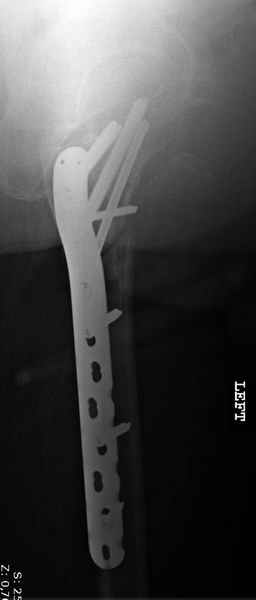

Re: [1/3] Перелом проксимального бедра

Применили проксимальную Synthes Locking plate, из-за множественных фрагментов посчитали более приемлемым в этом случае (клиника университетская, резиденты должны имет возможность созерцать разные варианты остеосинтеза).

Также старался минимизировать доступ на уровне перелома с субвастус доступом, диафиз фиксирован перкутанно, не стали гонятся за малым вертелом, как смог зафиксировал.

Перелом из четырех фрагментов, не стабильный (лекция Michael R. Baumgaertner, http://www.hwbf.org/ota/bfc/baumg/exp.htm), нужна стабильная фиксация.

Фиксация таких нестабильных чрезвертельных и reverse obliquity субтрохантерик переломов всегда была сложной задачей и ранее использовали Blade Plate. Но многие локальные общие ортопеды, к которым, в основном поступают такие больные, имели трудности с применением импланта, где необходимо было точная калькуляция по введению Blade и поэтому Synthes разработал Proximal Locking plate как альтернативу, где три проксимальные шурупа в разных направлениях создают концепцию угловой стабильности Blade Plate.

Со второго дня движения в суставе, контрольный осмотр через две недели и в зависимости от рентгенологического сращения, дозированную нагрузку с постепенным увеличением начнем через 5-6 недель.